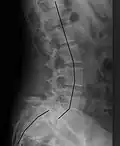

| X-ray of the lateral lumbar spine with a grade III anterolisthesis at the L5-S1 level | |

Spondylolisthesis refers to a condition in which one spinal vertebra slips out of place compared to another.[1] While some medical dictionaries define spondylolisthesis specifically as the forward or anterior displacement of a vertebra over the vertebra inferior to it (or the sacrum),[2][3] it is often defined in medical textbooks as displacement in any direction.[4][5]

Spondylolisthesis is graded based upon the degree of slippage of one vertebral body relative to the subsequent adjacent vertebral body.[6] Spondylolisthesis is classified as one of the six major etiologies: degenerative, traumatic, dysplastic, isthmic, pathologic, or post-surgical.[7] Spondylolisthesis most commonly occurs in the lumbar spine, primarily at the L5-S1 level, with the L5 vertebral body anteriorly translating over the S1 vertebral body.[7]

Severity

Classification by degree of the slippage, as measured as percentage of the width of the vertebral body:[17] Grade I spondylolisthesis accounts for approximately 75% of all cases.[7]

- Grade I: 0–25%

- Grade II: 25–50%

- Grade III: 50–75%

- Grade IV: 75–100%

- Grade V: greater than 100%